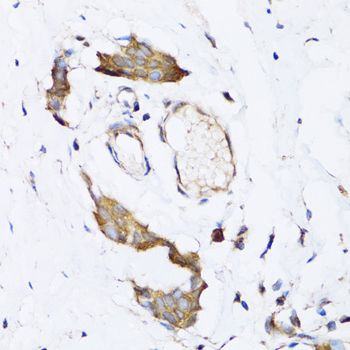

IHC-P analysis of human breast cancer tissue using GTX64704 ARD1A antibody.

Dilution : 1:100